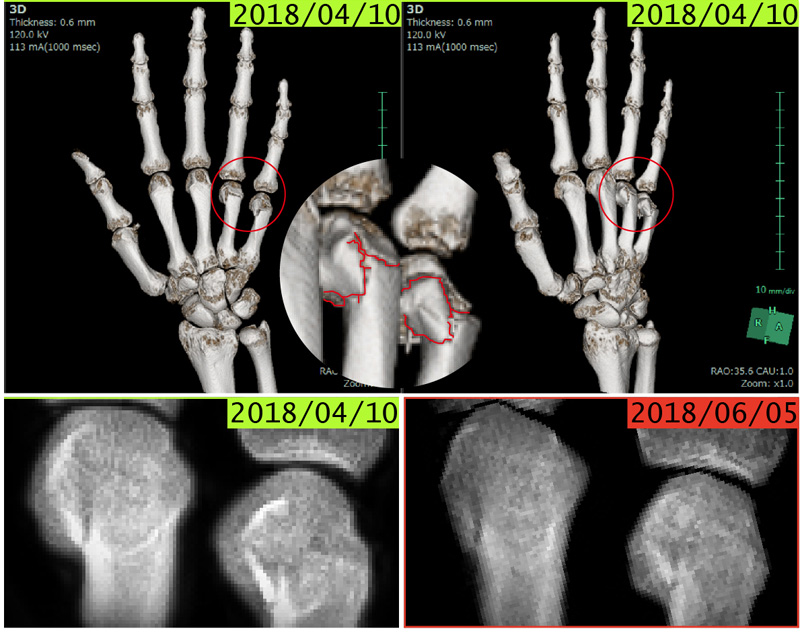

骨折も酵素玄米菜食で治しました!

2018年4月にHIRYU代表が右手薬指と小指を骨折した際、病院では麻酔を含めた一切の薬を使わず、整復とギブスのみの治療で済ませ、病院からは牛乳を飲んでカルシウムを摂るように勧められましたが、牛乳よりもカルシウム含有量の多いコマツナ(野菜で最もカルシウムが多い)を多くした酵素玄米菜食で完治させました。